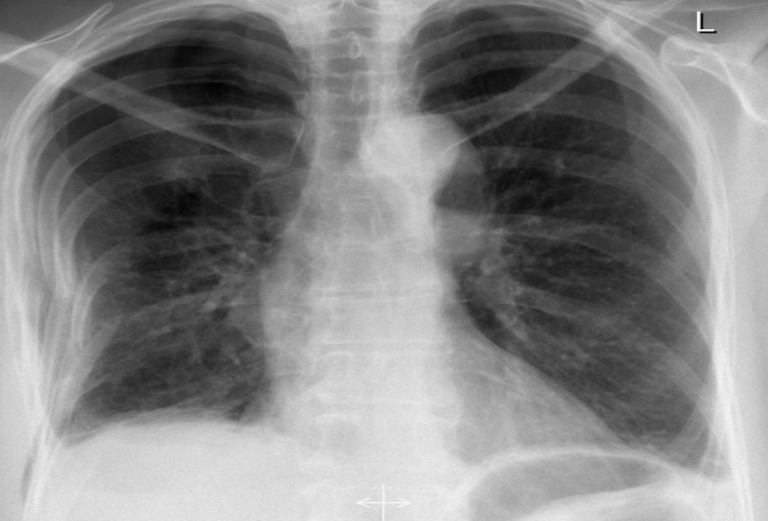

PA chest X-ray

Opacity on right side

Miniscus sign (indicates pleural effusion in PA view)

PA chest X ray

left lung lucency

veceral pleural line visible on left side

no tracheal divation and centralised mediastinum →so left sided simple pneumothorax

CP angle obliterated on left and no miniscus sign→air fluid leveling→pleural effusion on left side.

Left sided hydropneumothorax